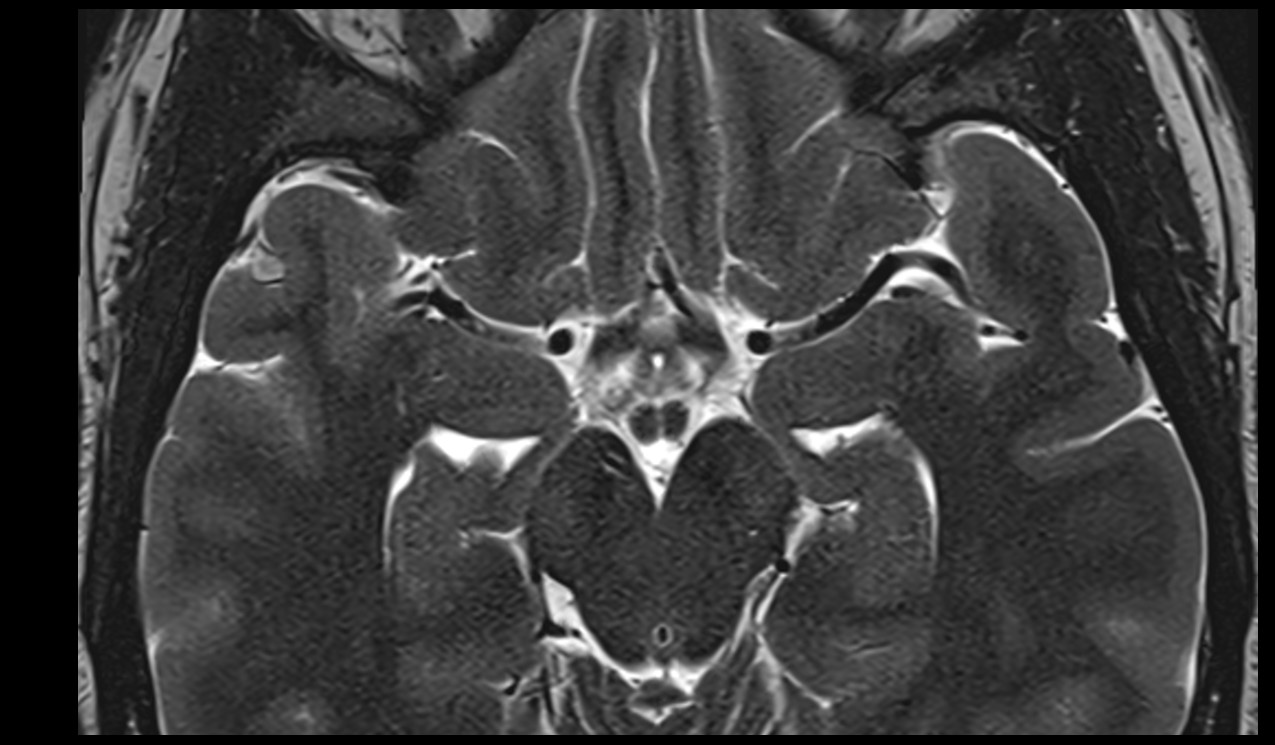

- Cerebellum

- Tonsil of cerebellum

- Middle cerebellar peduncle

- Inferior cerebellar peduncle